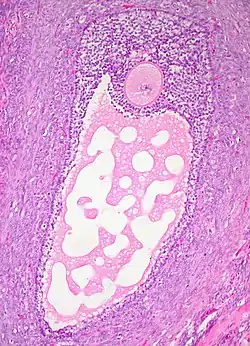

![]() Histology section of a mature ovarian follicle. The oocyte is the large, round, pink-staining cell at top center of the image. | |

Ovarian follicles are the basic units of female reproductive biology. Each of them contains a single oocyte (immature ovum or egg cell). These structures are periodically initiated to grow and develop, culminating in ovulation of usually a single competent oocyte in humans.[5] They also consist of granulosa cells and theca of follicle.

Once a month, one of the ovaries releases a mature egg (ovum), known as an oocyte. The nucleus of such an oocyte is called a germinal vesicle[6] (see picture).

The granulosa cells, in turn, are enclosed in a thin layer of extracellular matrix – the follicular basement membrane or basal lamina (fibro-vascular coat in picture). Outside the basal lamina, the layers theca interna and theca externa are found.